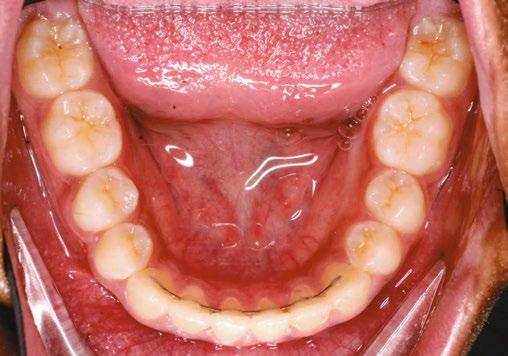

Figure 5: Final lower occlusal

Figure 6: Final left buccal

Figure 7: Final Center

Figure 4: Final right buccal

The treatment spanned a total of 12 appointments, which included all routine, emergency, and one reposition appointment. Notably, the reposition was necessitated by a clinician error in the delivery of a bonding jig, resulting in bracket misplacement. This underscores the technique sensitivity involved in indirect bonding systems and highlights the importance of clinician training and procedural verification. Emphasis on consistent technique evaluation and training among providers has proven instrumental in reducing such avoidable errors (Figures 4-6).

The results speak for themselves. Treatment planning is tighter. Turnaround is faster. Patient experience is smoother. And the time we used to spend managing systems is now spent building relationships and delivering results.